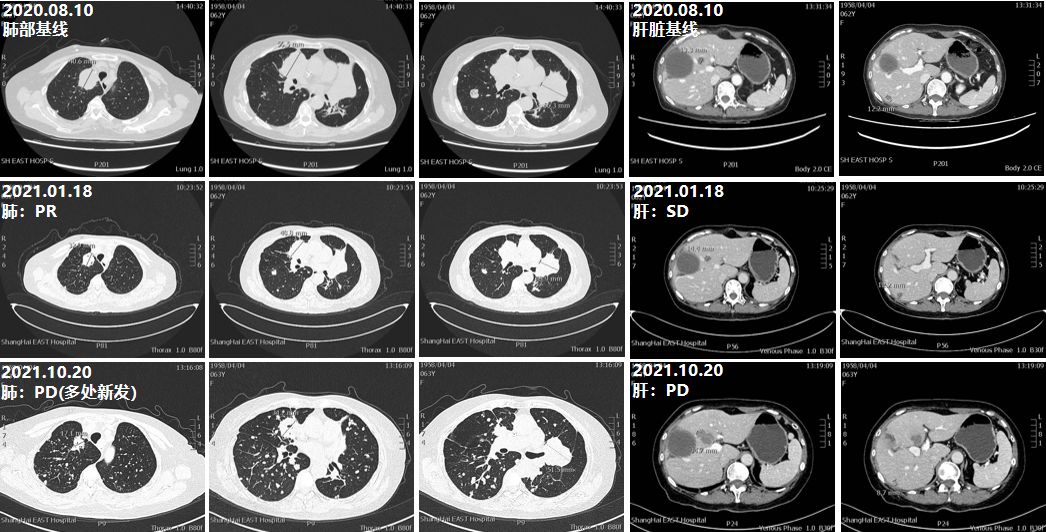

案例精要

该病例是一例直肠低-中分化腺癌(Ⅳ期),MSS型患者。从初诊行直肠癌根治性手术后复发的诊疗过程,患者中间历经了六线治疗,至今已经超过7年半的时间。在患者的姑息治疗中,除二线及六线治疗方案,余治疗方案均使用联合化疗方案。在初始治疗中,患者化疗的不良反应大且对化疗具有强烈排斥,故二线治疗为患者选用了不良反应较小的呋喹替尼单药治疗方案,获得了13个月的PFS。也正是这段“去化疗”的治疗阶段,赢得了后续治疗的依从性,患者三线及后续的治疗中,持续使用联合化疗方案,共为患者争取了近22个月的PFS,直至患者无法再耐受化疗。目前患者在使用靶向治疗联合免疫治疗,再次选择“去化疗”方案,同时是对后线治疗的新探索,也期待患者还能够在该治疗中有更优、更持久的生存获益。

图6 患者诊疗进程示意图